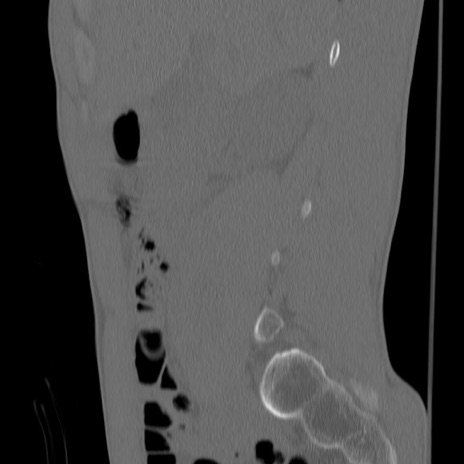

症例3 腰椎CT(矢状断像)

【症例】30歳代男性

【主訴】腰痛

【現病歴】本日旅行先で観光中に、友人と衝突し転倒し受傷。

【身体所見】麻痺なし、右下腿内側前面外側、左下腿内側に知覚鈍麻・しびれ

異常所見と診断は?

腰椎CT